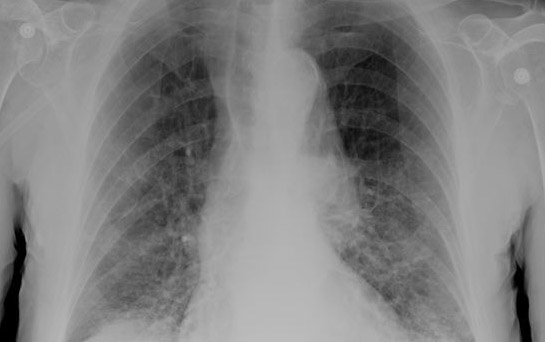

5. Tuberculosis

Over 2 million people die of TB every year. Over 8 million new cases develop each year and about 2 billion people are infected with TB. A chronic cough, chills, fever, weight loss and weakness are the main symptoms of this disease. The disease spreads through sneezing or coughing. Directly Observed Therapy Short-course – DOTS – is the internationally recommended approach to TB control.